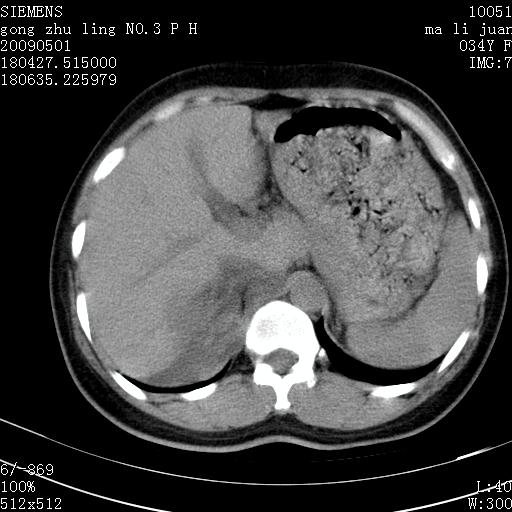

标题: CT19733:右肾碎裂

青年女性,骑摩托车摔伤。

右肾碎裂伤,包膜下血肿。

术中仅见右肾碎裂,肾蒂血管未见断裂。